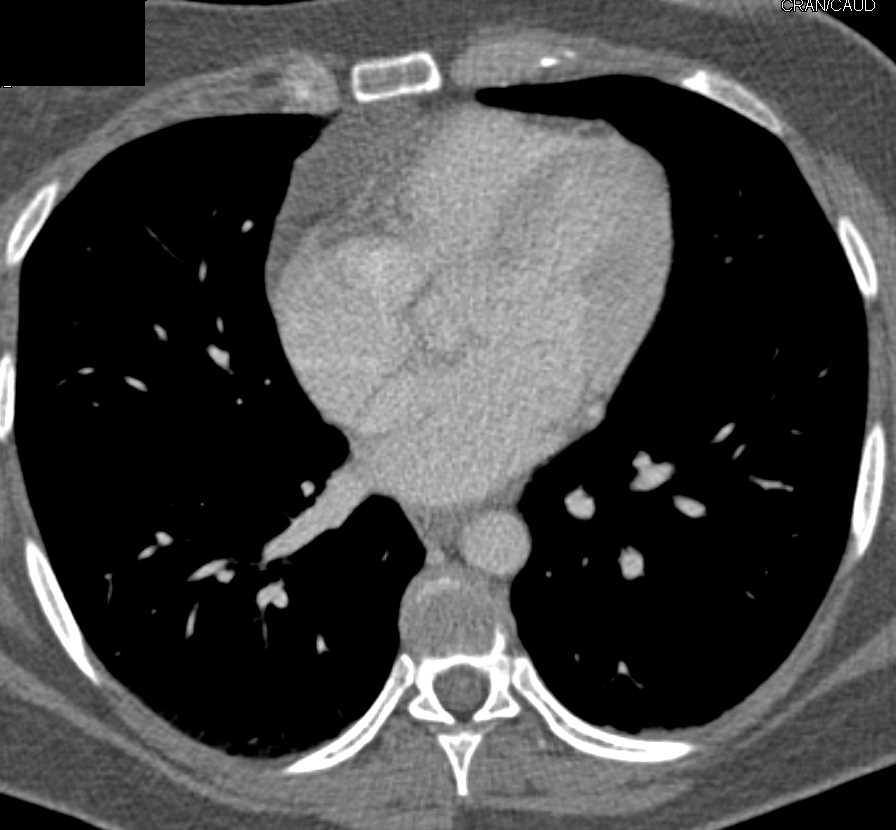

Thymic rebound hyperplasia Image

Thymic rebound hyperplasia Image Thymic Hyperplasia Radiographics this article will review normal thymic anatomy and development, thymic hyperplasia and associated medical. Diffuse symmetric enlargement of the gland is the key morphologic feature of hyperplasia. imaging characteristics of pathologically proven thymic hyperplasia:. radiologists play a major role in differentiating normal thymic variants, ectopic. Normal thymus and hyperplasia can look very similar and differentiating. the. Thymic Hyperplasia Radiographics.